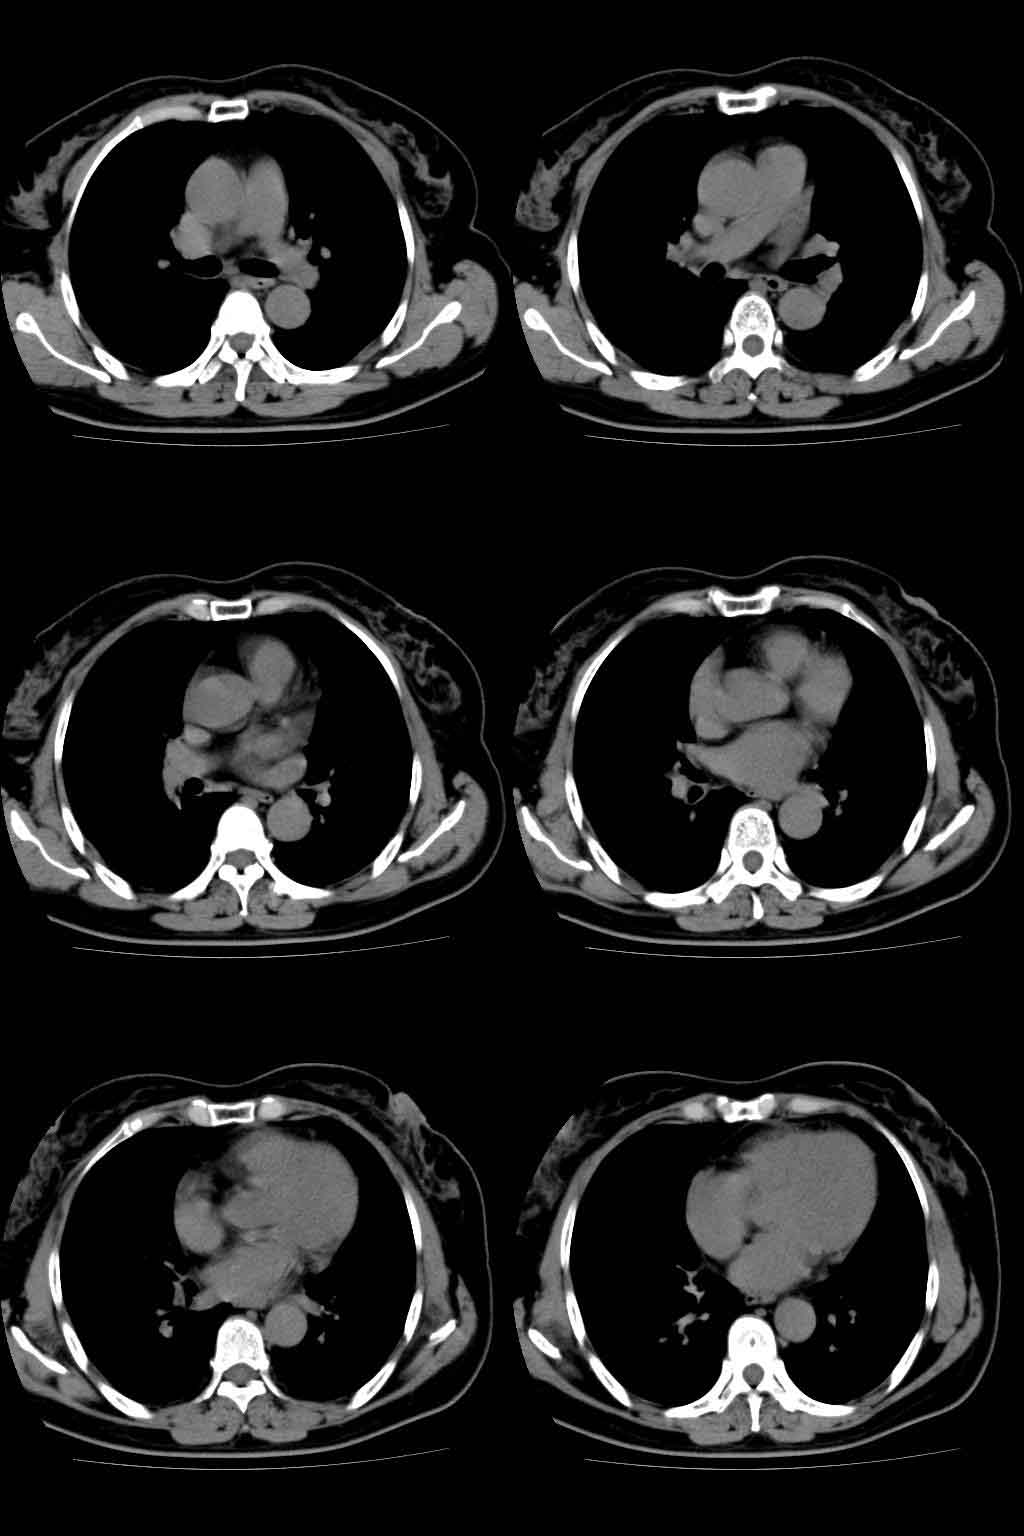

以下是引用lkc8963在2008-10-4 22:24:00的发言:[br]右下肺内基底段不规则软组织结块,肿瘤可能,建议增强鉴别于血管.